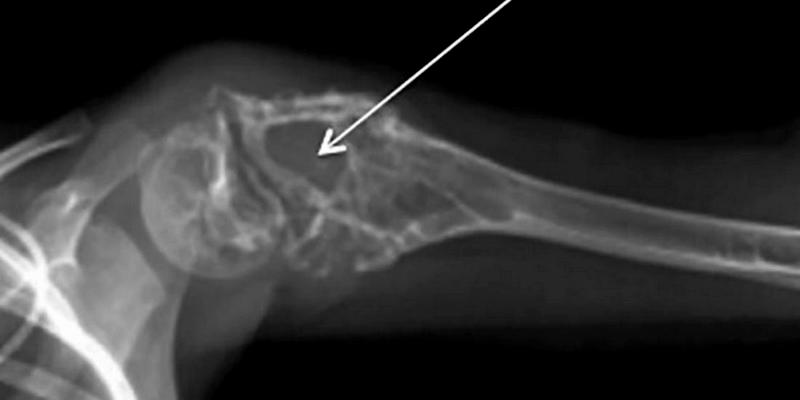

Jika ada indikasi kanker, dokter mungkin akan melakukan pemeriksaan lanjutan dengan tes pencitraan (imaging) untuk memastikannya. Tes pencitraan yang mungkin akan dilakukan oleh dokter misalnya pemindaian (scan) tulang, CT scan, MRI, atau pemeriksaan sinar-X.

Bila dipastikan adanya keberadaan tumor, dokter mungkin akan melakukan biopsi untuk mengambil sampel jaringan tumor tersebut. Sampel akan diperiksa di laboratorium untuk dilihat apakah di dalamnya terdapat sel-sel kanker.